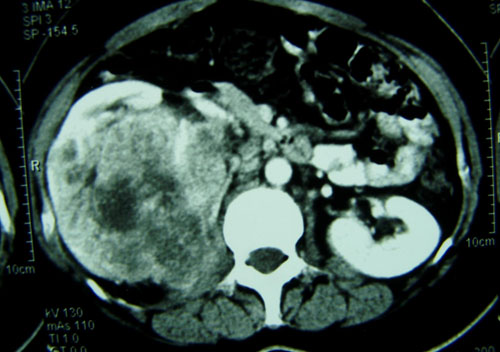

肾癌是泌尿生殖系常见恶性肿瘤之一,约占成人恶性肿瘤的3%,死亡率占癌症死亡的2%。目前肾癌最主要的治疗方法是肾根治性手术切除,然而肾癌起病隐匿,往往缺乏早期临床表现。大约30%的肾癌患者在确诊时已经发生转移,并且肾癌对放疗、化疗均不敏感。因此,急需深入探索肾癌发病的分子机制,找到肾癌早期诊断和治疗的分子靶标。

肾透明细胞癌是肾癌最常见的病理学类型,占肾癌的75%,SPOP是泛素连接酶E3家族成员Cul3与底物结合的桥梁蛋白,通过介导许多核蛋白的泛素化而促进它们的降解,从而参与调控细胞的多种功能。刘江过去的研究发现,SPOP在99%的肾透明细胞癌的肿瘤组织中过表达,而在对应的正常肾组织中表达很低,还发现转移性肾透明细胞癌SPOP仍过表达,这说明SPOP是透明细胞癌的标记分子。

该课题组的研究结果显示,核蛋白SPOP在肾癌组织中过量表达并错误定位在细胞质里。低氧微环境可以驱使过表达的SPOP蛋白在肾癌细胞质中大量累积。与核定位SPOP的促凋亡功能不同,胞质型SPOP能加速细胞增殖。此外,肾癌中SPOP还通过降解特殊途径来抑制细胞凋亡和促进细胞增殖,从而导致肿瘤产生。相反,敲除SPOP后能特异性杀死肾透明细胞癌,但对正常细胞影响较小。